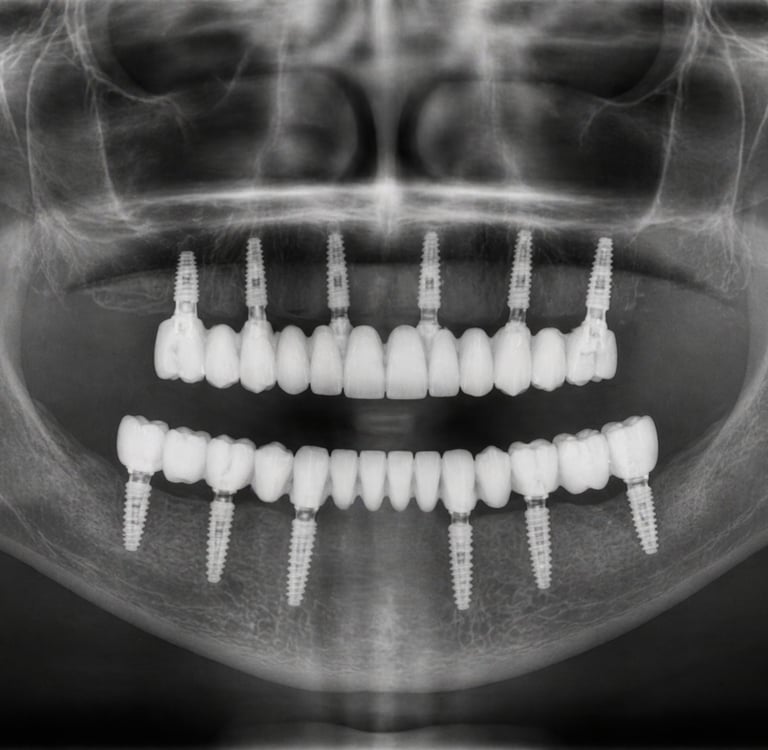

Un implant és una arrel artificial de titani que es col·loca a l'os per substituir la dent perduda. Sobre aquest implant es col·loca una corona que imita perfectament una dent natural.

Rehabilitacions completes (arcades senceres).

Estudi i diagnòstic digital: TAC dental + planificació

Col·locació de l'implant: cirurgia mínimament invasiva

Període d'integració: L'implant s'uneix a l'os

Col·locació de la pròtesi